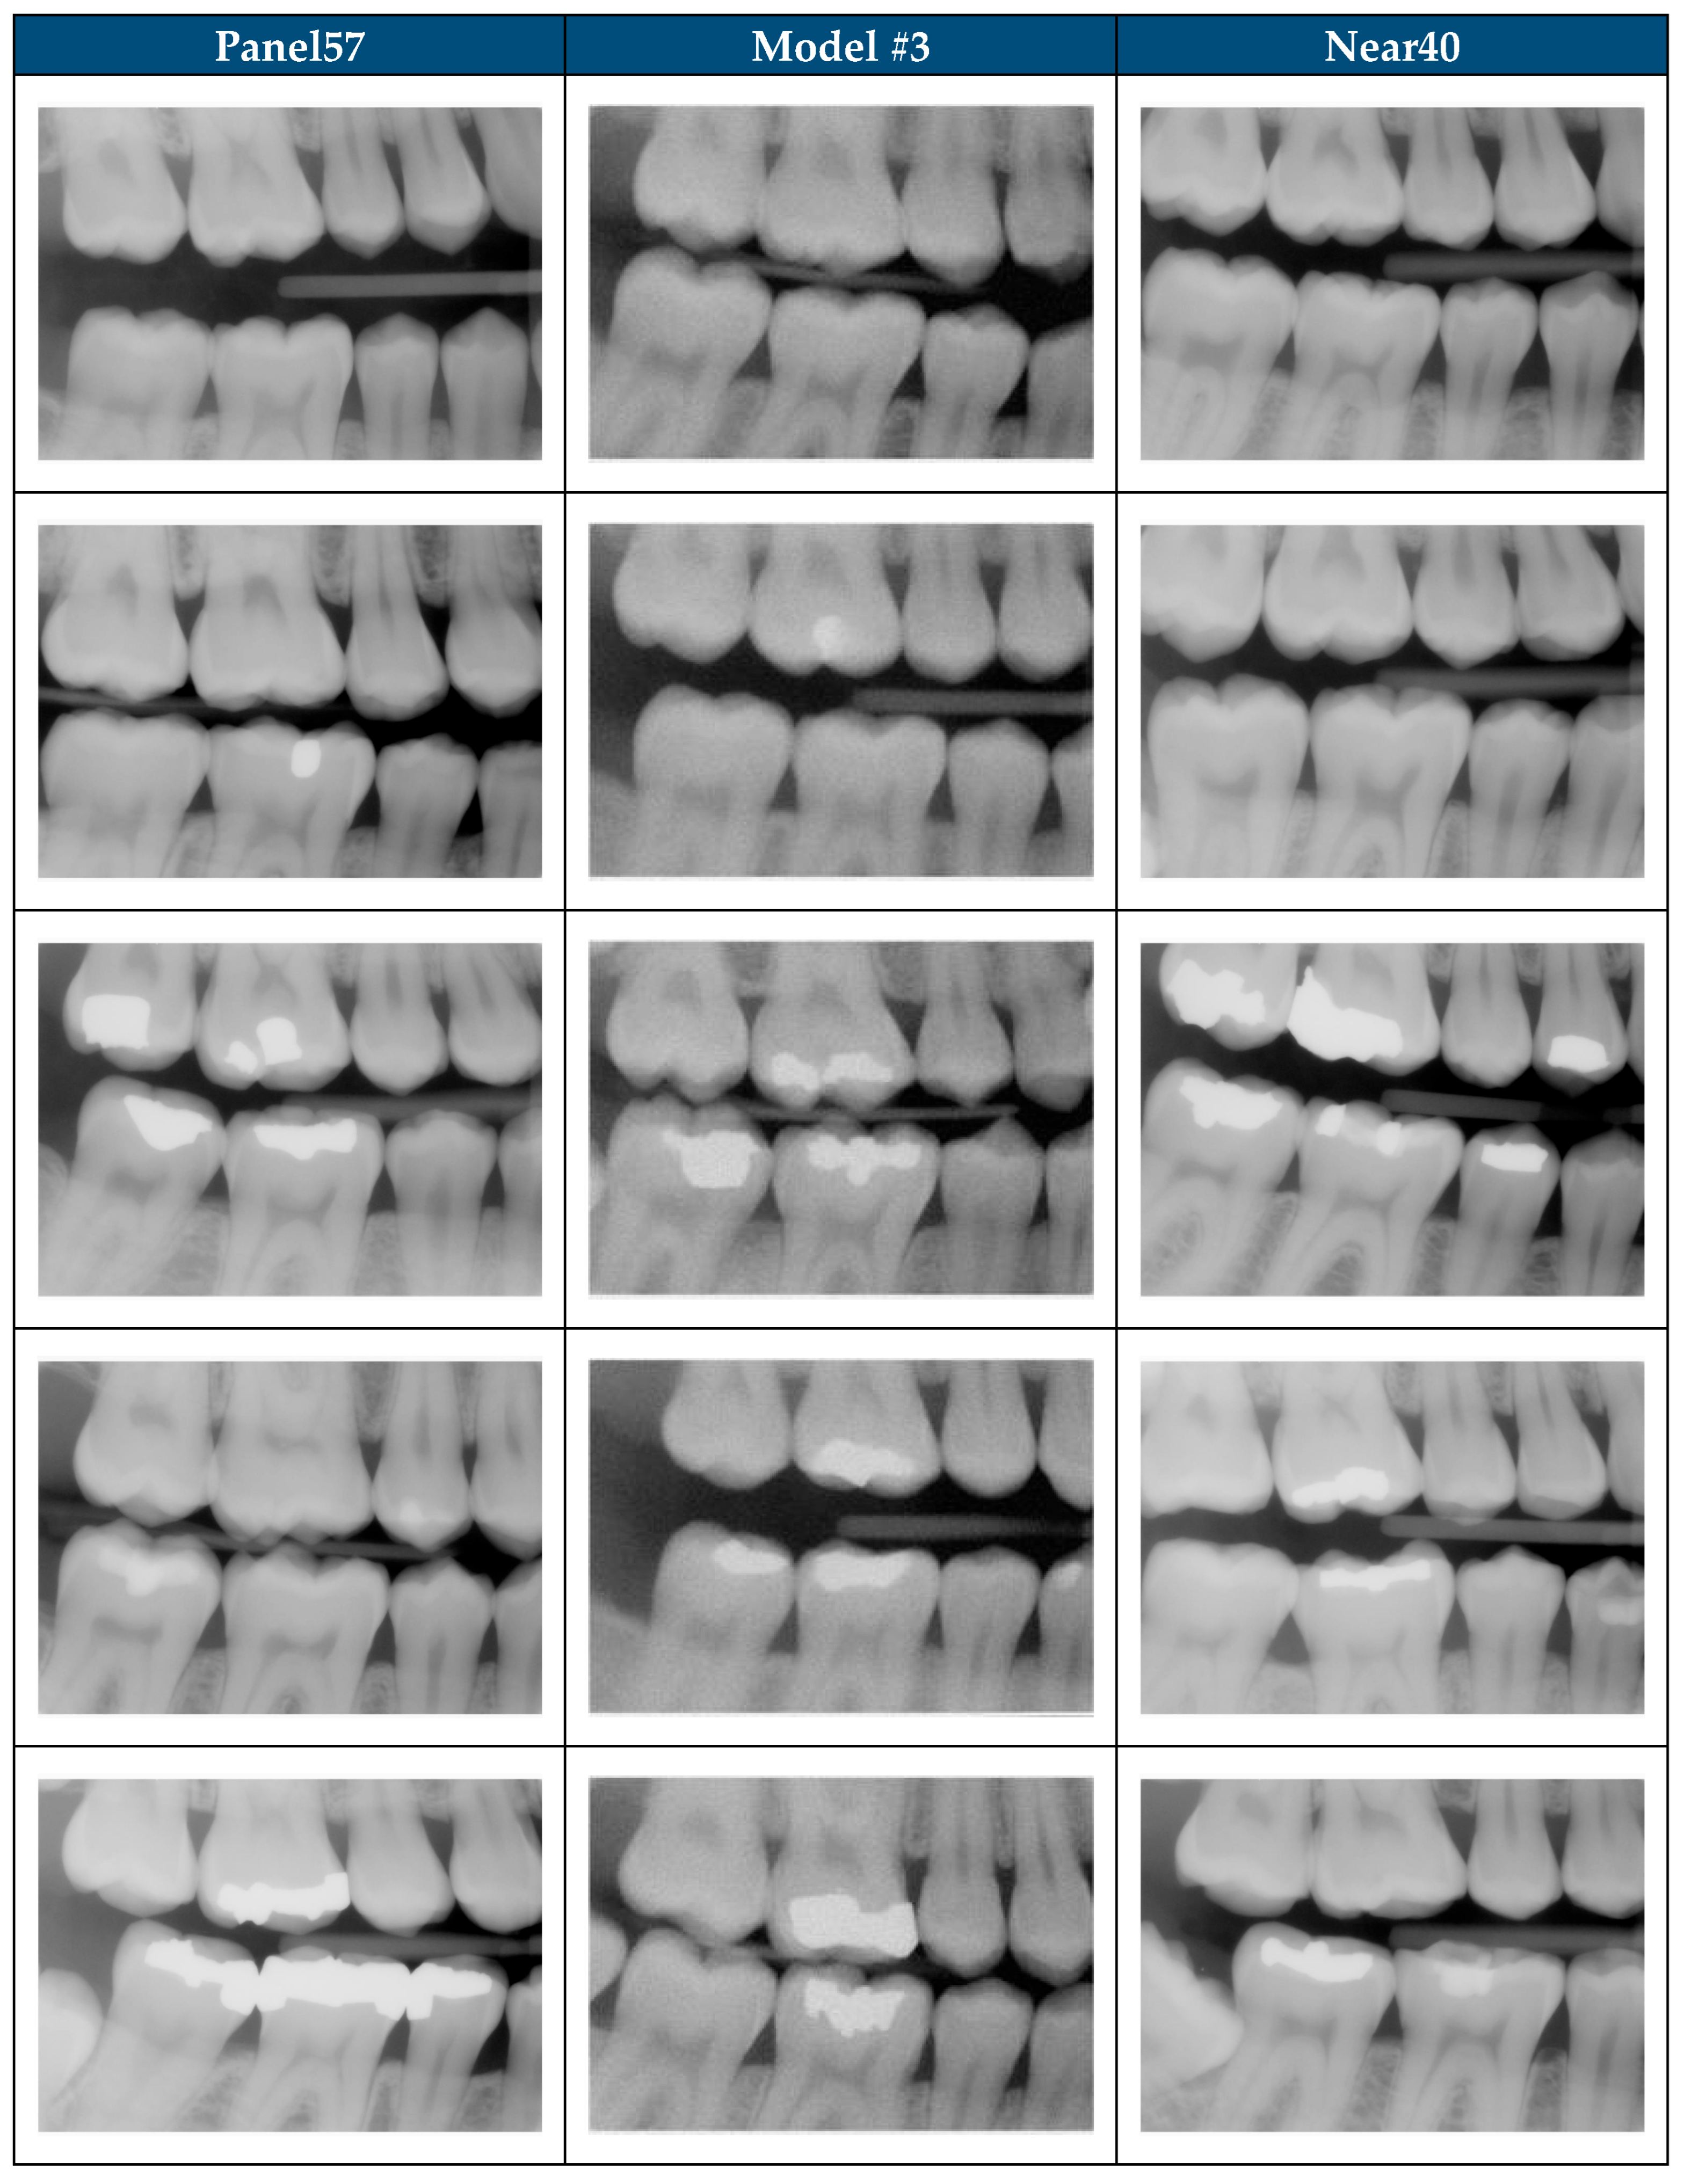

| Category | Description | Sample Images | |

|---|---|---|---|

| 1 | The image appears to be a realistic dental radiograph representative of the training data. (Looks real with no anatomic anomalies) | ![]() | ![]() |

| 2 | Image resembles a realistic dental radiograph representative of the training data but contains anatomical hallucinations or abnormalities. (Looks real but tooth count, order or anatomy is unreal) | ![]() | ![]() |

| 3 | Image is unrealistic but resembles the general appearance of dental radiograph represented in the training data. (Looks like a dental radiograph with features that are obviously fake) | ![]() | ![]() |

| 4 | The image is unrealistic, but portions of the image contain dental-related attributes. (At minimum portions of tooth anatomy are present) | ![]() | ![]() |

| 5 | No recognizable dental-related attributes. | ![]() | ![]() |

| Subset | Total Images | Selection Method | Training Exposure |

| All200 | 200 | BWRM radiographs that met image selection criteria | Model #1: all 200. Models #2–#3: Panel57 only |

| Panel57 | 57 | Expert-panel selected subset of All200 | Seen by all 3 models |

| Unseen143 | 143 | Remainder of All200 not in Panel57 | Unseen by Model #2 and Model #3 |

| Shift1000 | 1000 | Clinically acceptable BWRM excluded from model training | No exposure (all 3 models) |

| Near40 | 40 | Algorithmic-matched subset of Shift1000 (closest to All200) | No exposure (all 3 models) |

| Random40 (×5) | 40 | Five independent random subsets from Shift1000 | No exposure (all 3 models) |